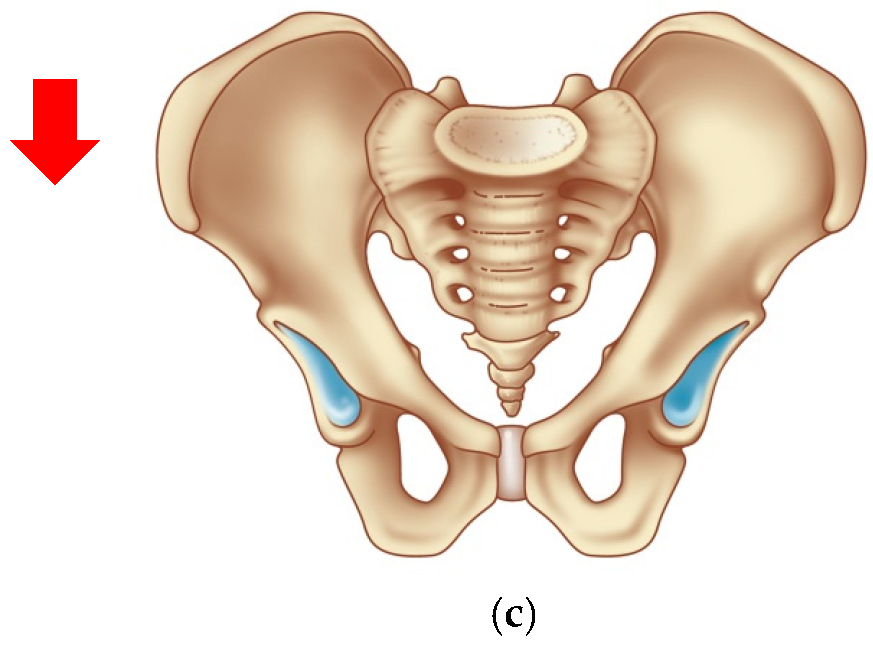

- Bone fixation of a marker